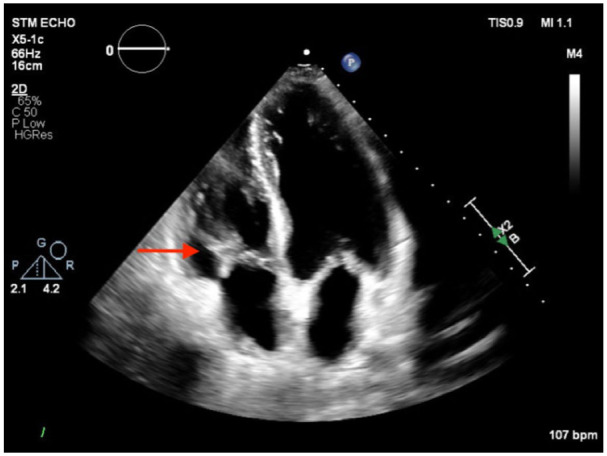

Pulmonary artery pseudoaneurysms (PAPAs) are rare and potentially fatal vascular complications that often require early detection. Most common etiologies are infection and trauma (including iatrogenic from procedures like pulmonary artery catheterization or lung biopsy). Early clinical signs include hemoptysis, dyspnea, and hemodynamic instability. Diagnostic workup should always include appropriate imaging modality, with computerized tomography (CT) and CT angiography as important diagnostic tools. Given the limited number of reported cases, treatment is not definitive and is largely guided by symptoms and patient present. In the case of massive hemoptysis, coil embolization or pulmonary vascular stenting is the preferred option. In the current case of asymptomatic PAPA, we will outline a more conservative approach to treating PAPA.